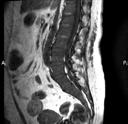

Ryc. 4.5. MRI – rozlany naciek szpiku.

Obecnie stanowi złoty standard w obrazowaniu zajęcia szpiku kostnego i zmian pozakostnych. Podanie środka kontrastowego nie jest potrzebne, ponieważ obrazy MRI cechują się wysoką rozdzielczością, dzięki czemu ocena nacieku szpiku tą techniką jest możliwa jeszcze przed pojawieniem się zmian litycznych kośćca w konwencjonalnym badaniu radiologicznym czy tomografii komputerowej. Zmiany ogniskowe uwi-

docznione w MRI korelują ze standardowymi czynnikami prognostycznymi (w tym cytogenetycznymi) i wynikami leczenia. Obecność więcej niż jednej zmiany ogniskowej w MRI jest najsilniejszym niekorzystnym czynnikiem prognostycznym w MRI, stanowiąc biomarker nowotworu uwzględniony w kryteriach rozpoznania szpiczaka. Obrazowanie kręgosłupa w MRI zapewnia ocenę potencjalnych powikłań mechanicznych złamań kręgów czy rozległych zmian w kanale kręgowym zagrażających kompresji rdzenia kręgowego i korzeni nerwów rdzeniowych.

Kwestię limitującą powszechne wykorzystanie rezonansu magnetycznego całego ciała we wstępnej diagnostyce szpiczaka plazmocytowego stanowi długi czas akwizycji danych, przekładający się także na większe ryzyko powstawania artefaktów ruchowych.